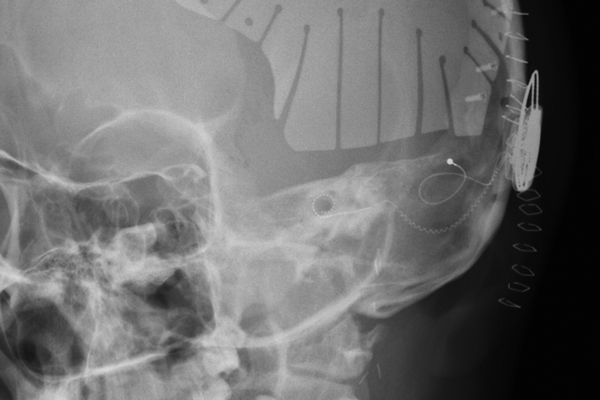

The role of objective measures and imaging to optimise cochlear implant outcomes